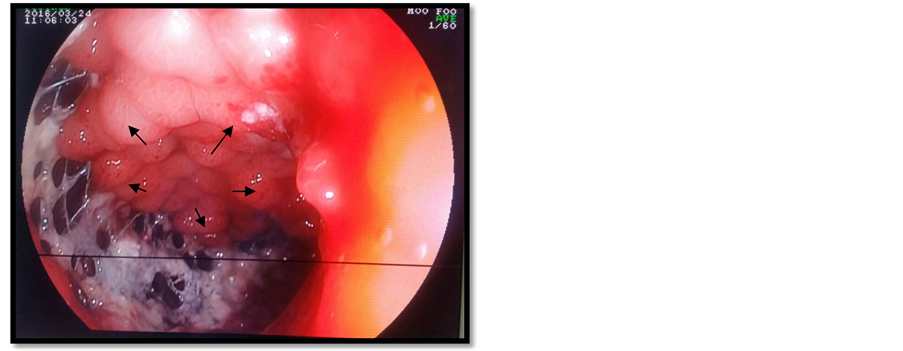

A duodenal prosthesis was introduced via an endoscopic retrograde cholangiopancreatography (ERCP) (Figure 2) but the procedure failed to catheterize the bile duct. An external draining of the bile was performed and biological parameters started to improve. Tumor markers, cancer antigen 19-9 (CA 19-9) and can- cer antigen 125 (CA 125) were high (121.3 ui/ml and 123.5 ui/ml). The histological analysis of a CT guided biopsy revealed that the tumor was an undifferentiated carcinoma (Figure 3).

Figure 3. Tumor proliferation arranged in tubules (Hematoxylin-eosin-saffron × 20).

As the presumed diagnosis was that of a primary bile duct tumor, the case was discussed in the local cancer multidisciplinary meeting, the oncologists suggested a breast recurrence and breast hormonal receptors were looked for by immunostaining. Luckily for the patient, hormonal receptors were positive (Figure 4) and she received a taxane first line chemotherapy (docetaxel 100 mg/m2 every 3 weeks

Figure 4. Expression of estrogen receptors (Immunostaining × 20).